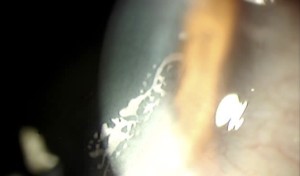

Grado 3

Opacidad gruesa (varias capas celulares) a más de 2 mm del margen del flap de color grisáceo, sin línea de demarcación y con zonas geográficas blanquecinas de células epiteliales necróticas. Los márgenes del flap suelen aparecer enrollados con apariencia blanco-grisáceo. Puede progresar hacia el eje visual y producir disminución de la visión. Requiere tratamiento.

Se podría diferenciar un grado 4cuando el CE se comporta de forma agresiva con rápida extensión hacia el eje visual pudiendo producir melting del flap. Esta forma clínica suele verse en el preoperatorio precoz y requiere tratamiento urgente.